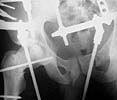

A 23 y.o. male after a car accident transferred to us from elsewhere at 4th day since the injury. He has the pelvic ring lesion including fracture of the left acetabulum, and ipsilateral femoral neck and shaft fractures - images attached. The shaft fracture is open grade II, debrided at the initial hospital - no sign of infection to date.

Our plan is to apply an external fixator with femoral extension, and maybe percutaneous fixation of the acetabulum. And some days later if no infection and patient is in stable condition - closed nailing of the shaft, lag screws for the neck. Your comments and suggestions are welcome.